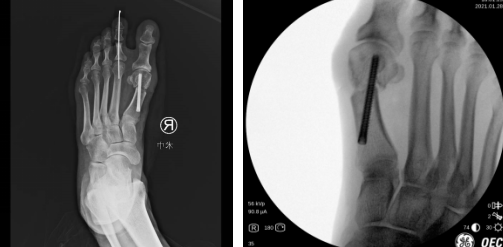

术后

第二天,徐明亮主任魏笛医生为患者进行了右足踇外翻截骨矫形内固定术及第2趾趾间关节成形术。术中,医生用低频超声骨刀清理骨赘,外移截骨,进行螺钉内固定,切口做了美容缝合,几乎看不到切口。

术后第二天,张大姐就完全感觉不到痛了,穿上配置的前足免负重鞋,在病区里活动。